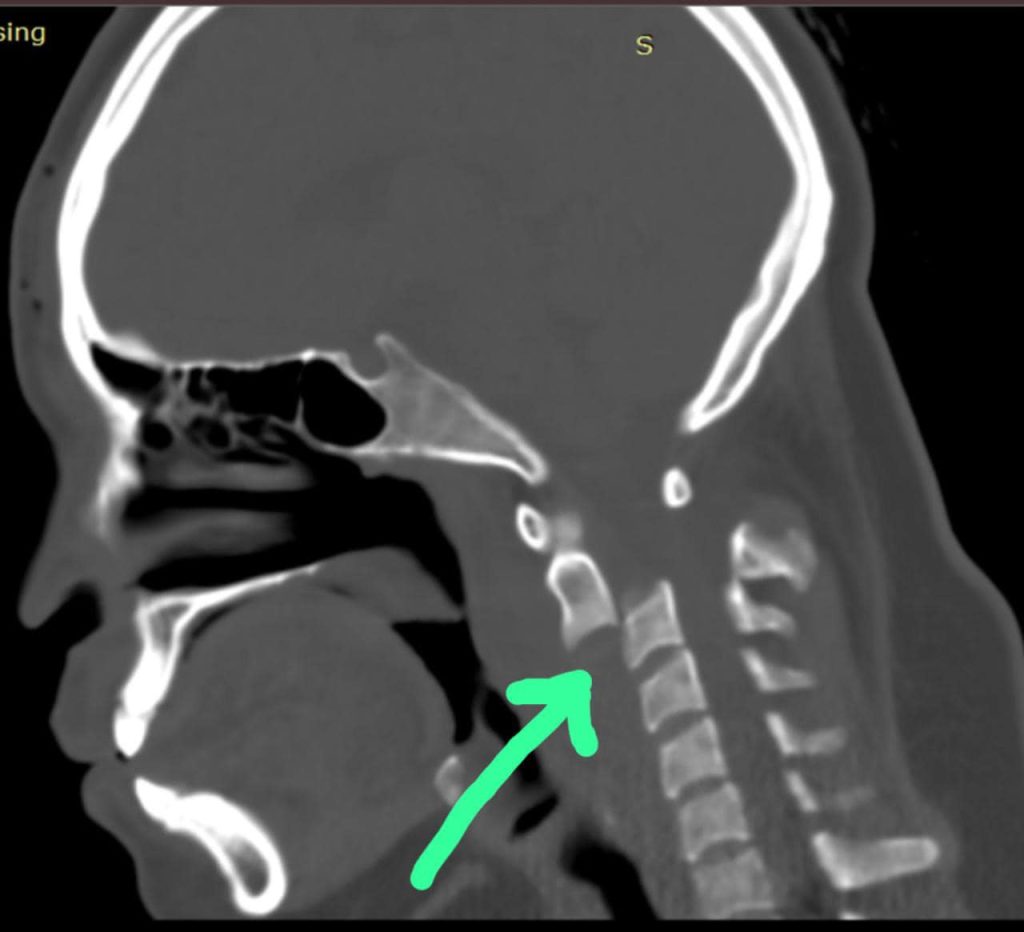

El Dr. Bernardo Herrera Juárez, médico adscrito al Servicio de Traumatología y Ortopedia de este centro médico, y quien lideró dicha intervención quirúrgica relata que la paciente ingresó con una luxación en el cuello, un área sumamente peligrosa, ya que se encuentran las vértebras cercanas al cráneo y los centros respiratorios y del corazón, “si estos se dañan es sumamente difícil que una persona pueda volver a tener movilidad o inclusive sobrevivir”.

Durante la primera cirugía le colocaron un halo cefálico en el cráneo, que permitió dar tracción a la vértebra luxada y acomodarla nuevamente en su lugar, dos días después se realizó un segundo procedimiento en el que se le colocó una caja especial de titanio expandible y bloqueada para fijar la vértebra, aparato diseñado y donado por el hospital con un valor de 45 mil pesos.

“Otros pacientes con una lesión mucho menor tienen pronósticos no favorables con sección medular y sin movilidad para siempre en las extremidades; en el caso de esta paciente, tras investigaciones médicas realizadas, logramos crear un aparato (caja intersomatica bloqueada) que mejorará la vida de pacientes con este diagnóstico y tener una mayor esperanza de recuperación”, mencionó el Dr. Bernardo en entrevista para Central Q Noticias.